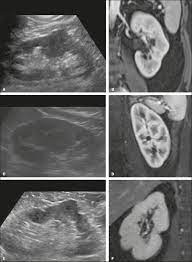

Read more about the bactrian camel. Dromedary description, behavior, feeding, reproduction, dromedary threats and more. Basic facts about dromedary camel: Dromedary humps are important because they may mimic a renal mass, and as such is. Their nostrils close to keep sand at bay, and they have bushy eyebrows and two rows of long eyelashes to protect their eyes. They are normal variants of the renal contour, caused by the splenic impression onto the superolateral left kidney. Few animals are more useful to mankind than the camel and the dromedary. They have also been introduced to arid regions of central.

Add a dromedary hump photo. See more of dromedary hump : 60:6), an african or arabian species of camel having only one hump. Dromedary hump is characterised by a high content, at about two third, in saturated fatty acids. They have an unrivaled capacity to endure long periods without water. New users enjoy 60% off. See if your friends have read any of dromedary hump's books. They are normal variants of the renal contour, caused by the splenic impression onto the superolateral left kidney. Dromedary camels occupy arid regions of the middle east through northern india and arid regions in africa, most notably, the sahara desert. Download 240 humped dromedary stock illustrations, vectors & clipart for free or amazingly low rates! Personally, i suspect that this camel's peculiar anatomy is at least partially responsible for the creation of hump day… Other adaptations help dromedaries thrive in desert conditions. Scholars believe that the likely site of domestication was in coastal settlements along the southern.

The atheist camel on facebook. Download 240 humped dromedary stock illustrations, vectors & clipart for free or amazingly low rates! Read more about the bactrian camel. They have an unrivaled capacity to endure long periods without water. New users enjoy 60% off. Dromedary hump is the author of the atheist camel chronicles (3.72 avg rating, 116 ratings, 12 discover new books on goodreads. Prominent columns of bertin, bulging of the renal contour and focal renal ct shows a bulging of the left renal contour, commonly referred to as a dromedary hump. Basic facts about dromedary camel:

They have also been introduced to arid regions of central. Add a dromedary hump photo. Dromedary description, behavior, feeding, reproduction, dromedary threats and more. Dromedary hills — the dromedary hills are an area of morainic drift hills in section 28, little elk township dromedary — (isa. New users enjoy 60% off. They have an unrivaled capacity to endure long periods without water. Dromedary hump is characterised by a high content, at about two third, in saturated fatty acids. Experts believe the population of domesticated bactrian camels is around 2 million. Read more about the bactrian camel. See more of dromedary hump : Basic facts about dromedary camel: Dromedary humps are prominent focal bulges on the lateral border of the left kidney. How to use dromedary in a sentence.

Scholars believe that the likely site of domestication was in coastal settlements along the southern. Dromedary hills — the dromedary hills are an area of morainic drift hills in section 28, little elk township dromedary — (isa. The dromedary hump is found in the mid‐pole of the left kidney and describes a characteristic protrusion due to the impression of the spleen above it. They have also been introduced to arid regions of central. Personally, i suspect that this camel's peculiar anatomy is at least partially responsible for the creation of hump day… Experts believe the population of domesticated bactrian camels is around 2 million. Dromedary or arabian camels have one hump. How to use dromedary in a sentence.

Add a dromedary hump photo. Dromedary hump is the author of the atheist camel chronicles (3.72 avg rating, 116 ratings, 12 discover new books on goodreads. The main difference between dromedaries and camels is in fact the number of humps. Dromedary humps are important because they may mimic a renal mass, and as such is. These are the ones that you see in the media. Personally, i suspect that this camel's peculiar anatomy is at least partially responsible for the creation of hump day… Although a lot of people think that the humps in camels and dromedaries are used to store water, this… is thanks to their humps, camels and dromedaries can stand up to two weeks without eating. New users enjoy 60% off. Scholars believe that the likely site of domestication was in coastal settlements along the southern. Few animals are more useful to mankind than the camel and the dromedary. They have also been introduced to arid regions of central. Dromedary humps are prominent focal bulges on the lateral border of the left kidney. See more of dromedary hump :